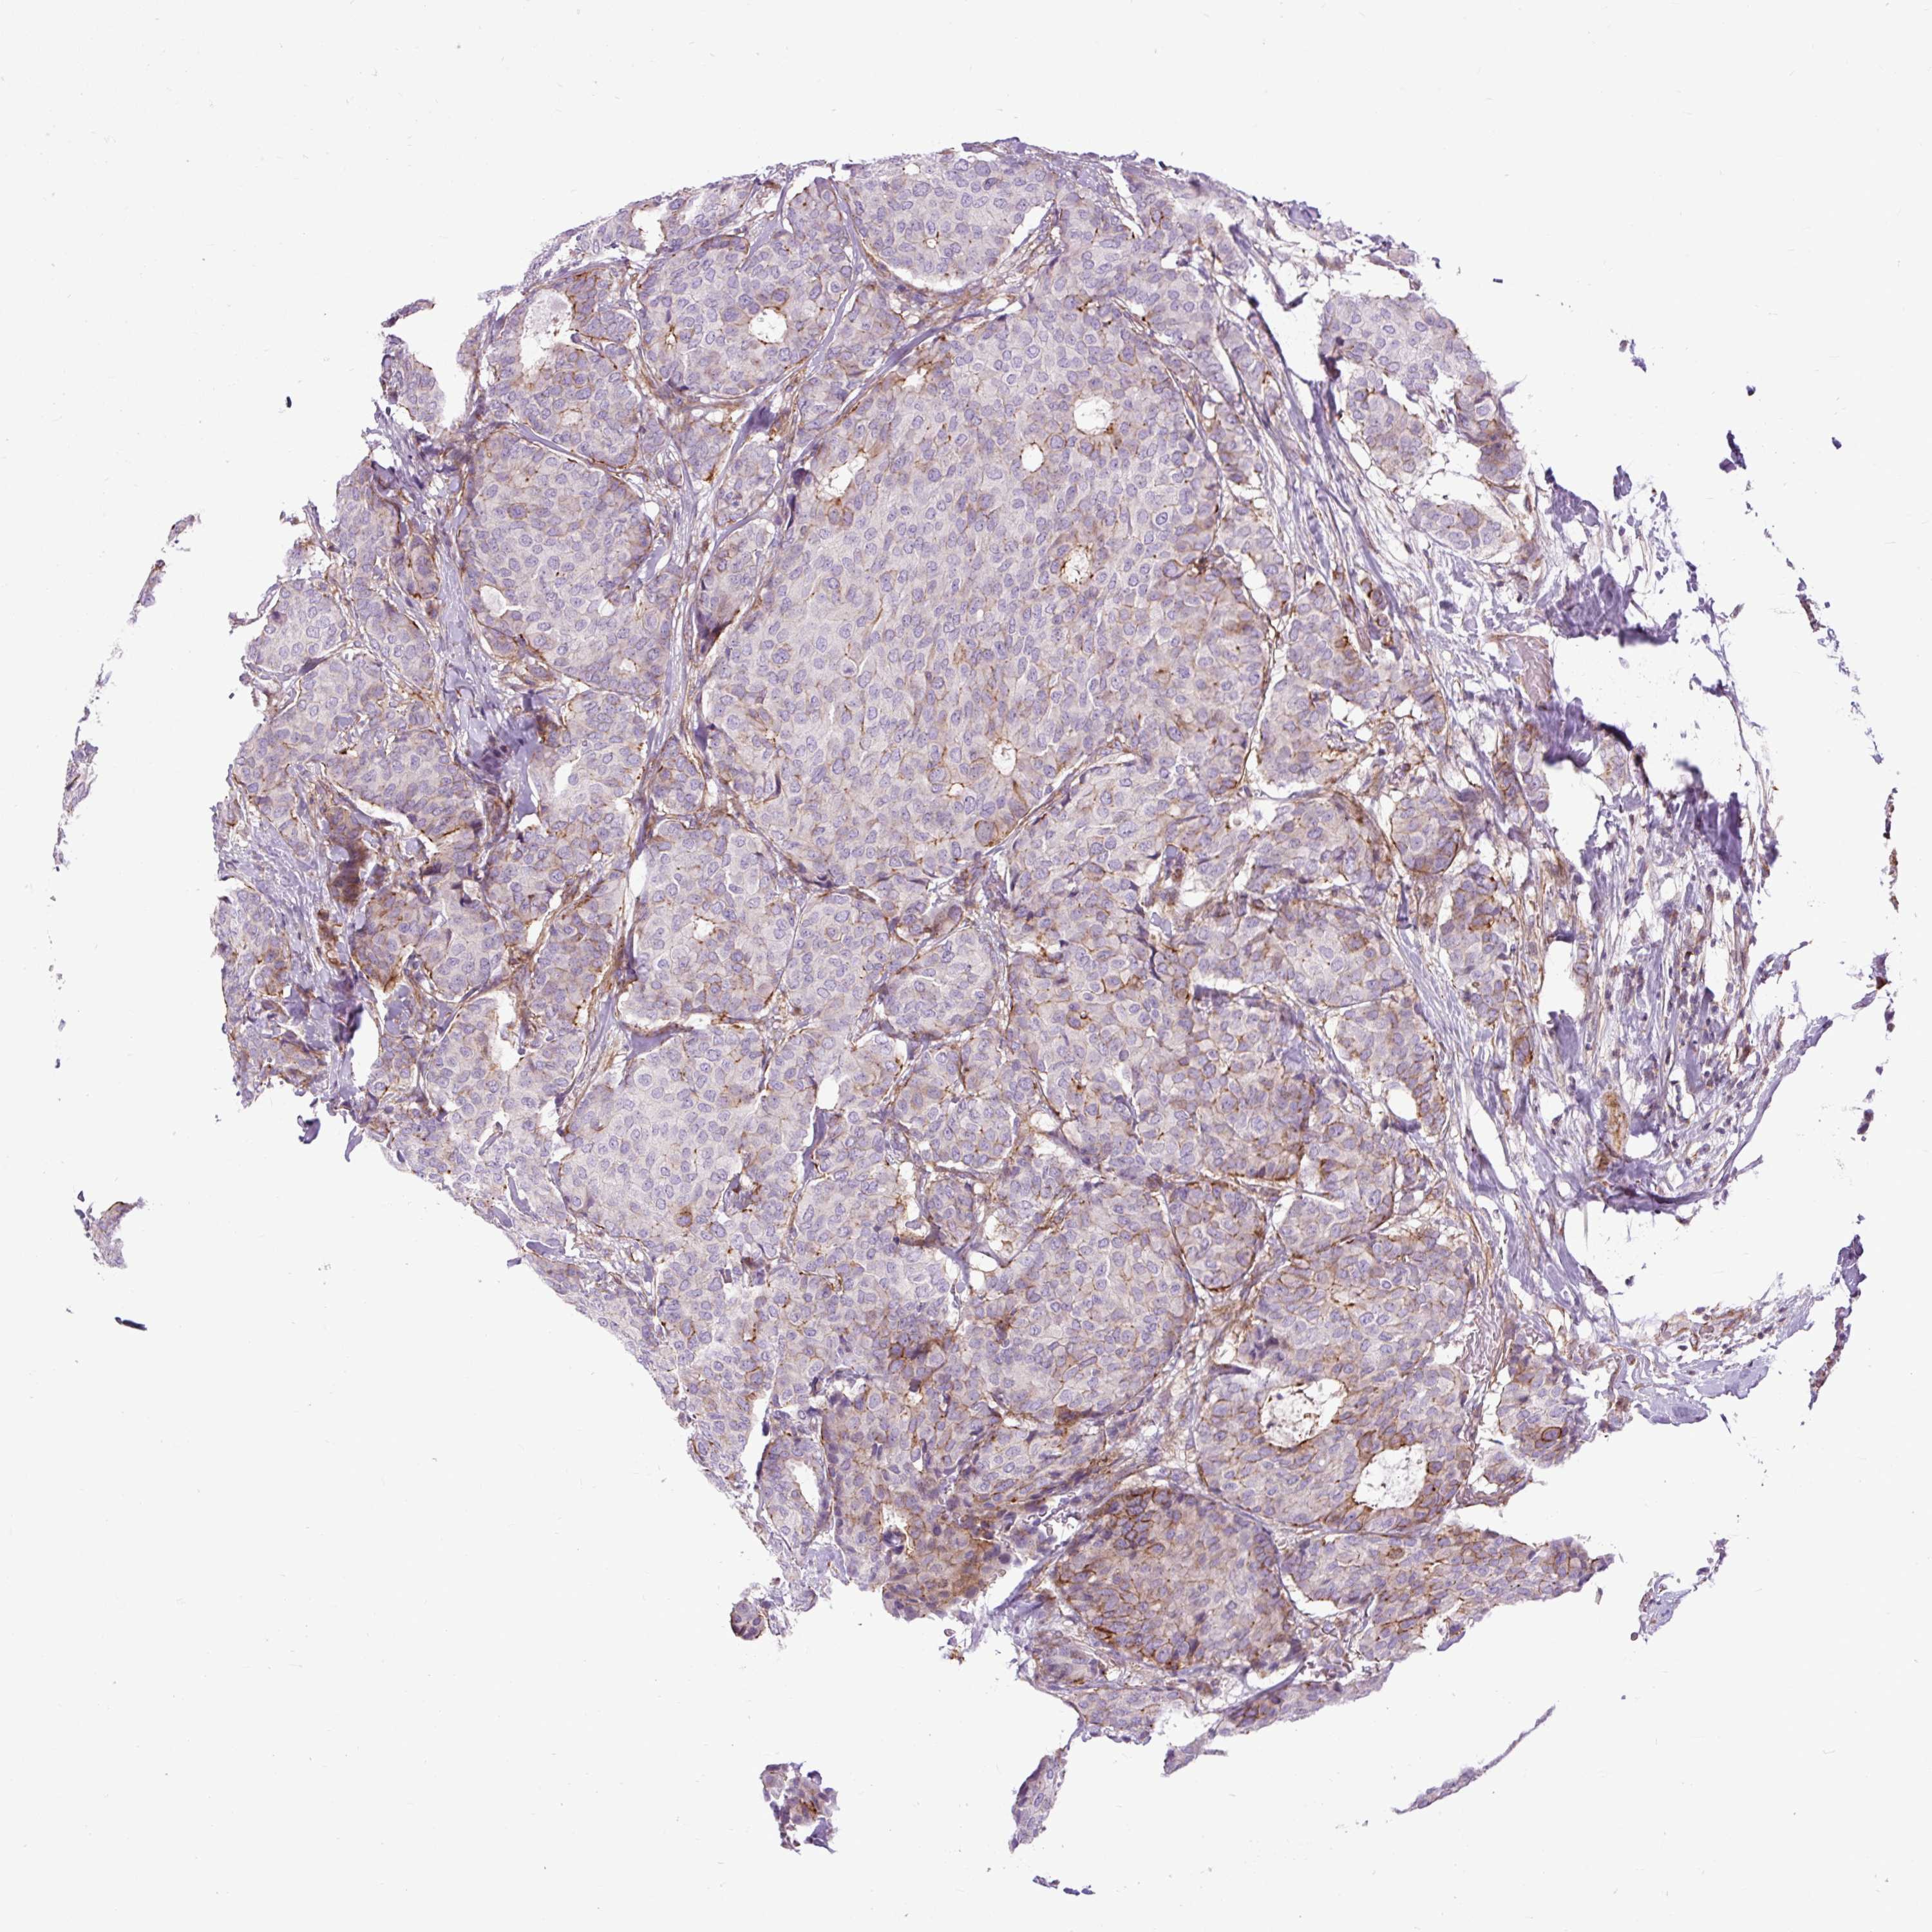

CANCER BREAST CANCER Show tissue menu

Breast cancer

Human cancer